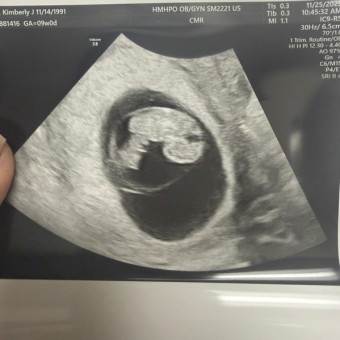

Kimberly Lee

Spring, TX

July 4, 2026

A third one was not necessarily in our plans right now, but God has His own! We are so excited to add another sweet little girl to our family.